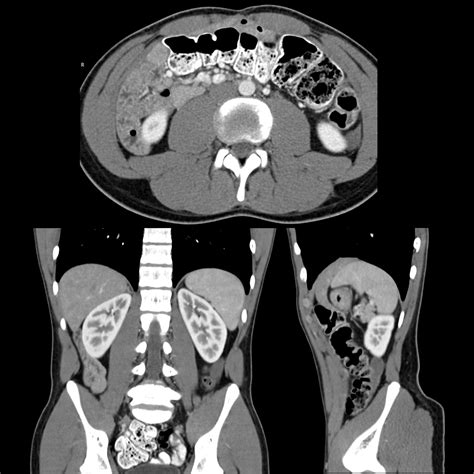

• Ultrasound: This imaging test uses sound waves to create images of the inside of the body. It can help locate an undescended testicle.

• Magnetic Resonance Imaging (MRI): An MRI uses magnetic fields and radio waves to produce detailed images of the body. It can be used to locate an undescended testicle that is not visible on an ultrasound.

• Laparoscopy: This is a minimally invasive surgical procedure that involves inserting a small camera into the abdomen to visualize the testicle.

In some cases, undescended testicle pics from imaging tests can be crucial in diagnosing the condition. These images provide a clear visual representation of the testicle's location, aiding in the development of an appropriate treatment plan.